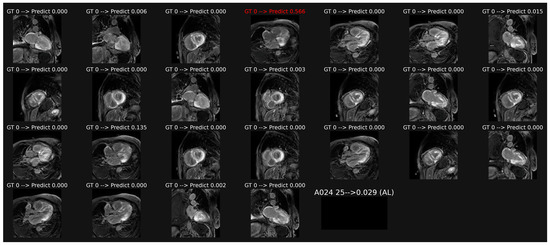

3.2. Classification of LGE Images

3.5. Analysis of Saliency Maps for cineMR Images